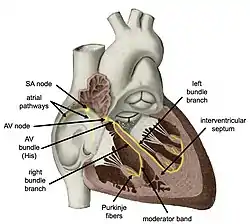

Components of the heart's conduction system | |

The cardiac conduction system (CCS, also called the electrical conduction system of the heart)[1] transmits the signals generated by the sinoatrial node – the heart's pacemaker, to cause the heart muscle to contract, and pump blood through the body's circulatory system. The pacemaking signal travels through the right atrium to the atrioventricular node, along the bundle of His, and through the bundle branches to Purkinje fibers in the walls of the ventricles. The Purkinje fibers transmit the signals more rapidly to stimulate contraction of the ventricles.[2]

Structure

Electrical signals arising in the SA node (located in the right atrium) stimulate the atria to contract. Then the signals travel to the atrioventricular node (AV node), which is located in the interatrial septum. After a short delay that gives the ventricles time to fill with blood, the electrical signal diverges and is conducted through the left and right bundle branches of His to the respective Purkinje fibers for each side of the heart, as well as to the endocardium at the apex of the heart, then finally to the ventricular epicardium; causing the ventricles to contract.[2] These signals are generated rhythmically, which results in the coordinated rhythmic contraction and relaxation of the heart.

SA node: P wave

Under normal conditions, electrical activity is spontaneously generated by the SA node, the cardiac pacemaker. This electrical impulse is propagated throughout the right atrium, and through Bachmann's bundle to the left atrium, stimulating the myocardium of the atria to contract. The conduction of the electrical impulses throughout the atria is seen on the ECG as the P wave.[5][7]

As the electrical activity is spreading throughout the atria, it travels via specialized pathways, known as internodal tracts, from the SA node to the AV node.

AV node and bundles: PR interval

The AV node functions as a critical delay in the conduction system. Without this delay, the atria and ventricles would contract at the same time, and blood wouldn't flow effectively from the atria to the ventricles. The delay in the AV node forms much of the PR segment on the ECG, and part of atrial repolarization can be represented by the PR segment.

The distal portion of the AV node is known as the bundle of His.[8] The bundle of His splits into two branches in the interventricular septum: the left bundle branch and the right bundle branch. The left bundle branch activates the left ventricle, while the right bundle branch activates the right ventricle.

The left bundle branch is short, splitting into the left anterior fascicle and the left posterior fascicle. The left posterior fascicle is relatively short and broad, with dual blood supply, making it particularly resistant to ischemic damage. The left posterior fascicle transmits impulses to the papillary muscles, leading to mitral valve closure. As the left posterior fascicle is shorter and broader than the right, impulses reach the papillary muscles just prior to depolarization, and therefore contraction, of the left ventricle myocardium. This allows pre-tensioning of the chordae tendinae, increasing the resistance to flow through the mitral valve during left ventricular contraction.[5] This mechanism works in the same manner as pre-tensioning of car seatbelts.

Purkinje fibers/ventricular myocardium: QRS complex

The two bundle branches taper out to produce numerous Purkinje fibers, which stimulate individual groups of myocardial cells to contract.[5]